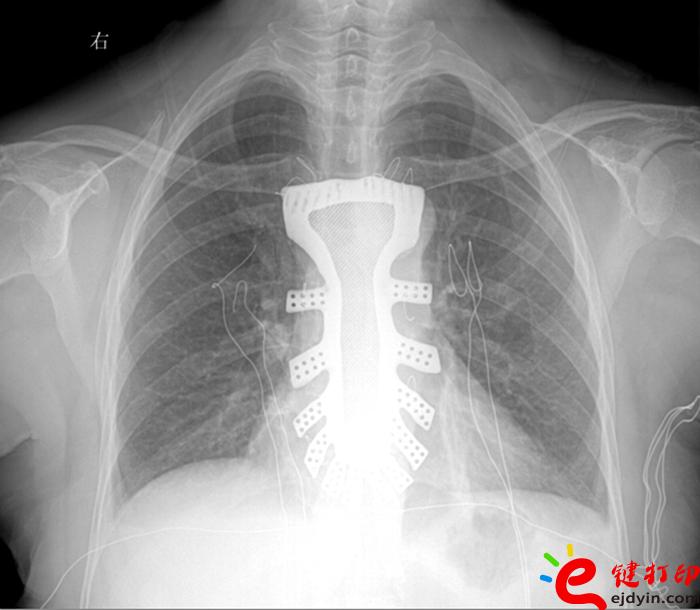

據王小平教授介紹,唐都醫院3D打印小組經過精密計算患者胸骨的大小、形狀等,充分研究討論,歷時一周,為患者設計出了手術使用的3D胸骨模型,并與西北工業大學凝固技術國家重點實驗室合作,為患者打印出了1:1鈦合金胸骨模型。隨后,又對該模型進行了一系列嚴密的醫學處理。

“手術歷時2.5小時,對患者的胸骨進行了整體切除,置換了鈦合金胸骨,目前患者恢復良好,未發現任何并發癥?!蓖跣∑浇淌诜Q,根據專業機構檢索,該手術是世界首例針對胸骨腫瘤疾病,將3D打印的可植入性鈦合金胸骨植入人體,實現病變胸骨的整體置換的手術。該手術的成功意味著未來將會為更多的胸骨腫瘤患者帶來福音。